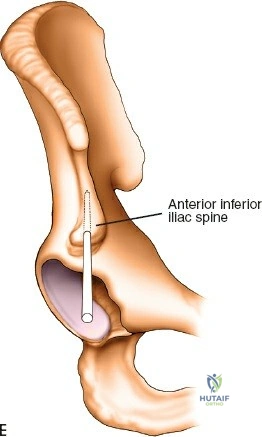

Proximal Humerus Pin Placement

1. Identify the safe zone on the lateral aspect of the proximal humerus, distal to the axillary nerve.

2. Make a longitudinal incision over the lateral aspect of the greater tuberosity or proximal diaphysis.

3. Bluntly dissect through the deltoid muscle fibers down to the bone.

4. Insert the drill sleeve, pre-drill with a 3.5 mm or 4.0 mm bit, and insert a 5.0 mm half pin.

5. Confirm bicortical purchase with fluoroscopy.